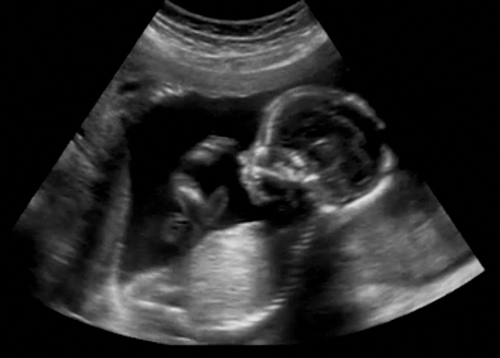

【click...】 お腹の中にいる赤ちゃんが、お母さんの身に起こる 様々な事象をすでに認識しているとしたら.... それだけではなく、お腹に入る以前の記憶を持っているとしたら、 あなたはどう感じますか?